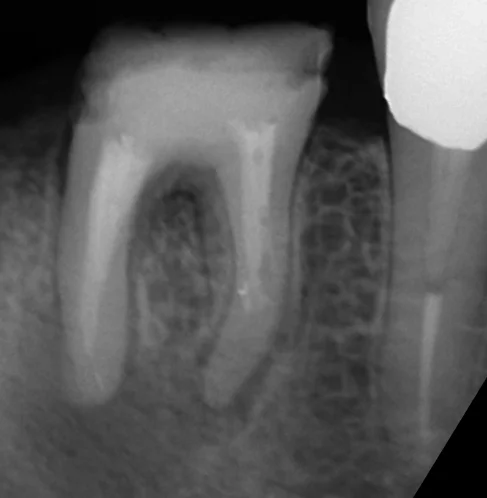

そしてその結果が、こちらです。

肝心の根尖病巣が入り切っていませんが、画像のトリミングの失敗です(笑)

注目して頂きたいのは、近心根ですが、実は根尖(根の先)まで全く行けていません。

大体2/3程度まで進んだのですが、それ以上は根管が石灰化していたため、全然進めませんでした。

それでも違和感が消失するのはそれなりに理由があるのですが、そこらへんはまたどこかでブログに書きたいと思います。